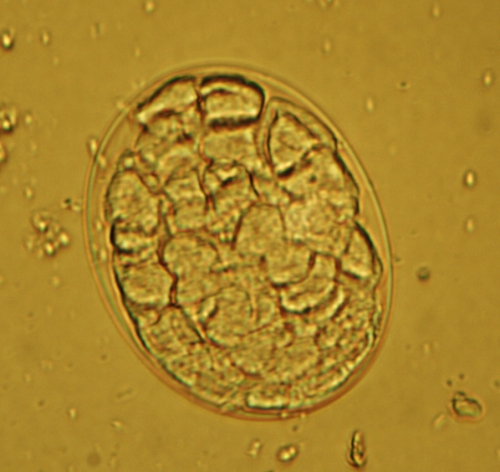

糞便検査による顕微鏡検査で虫卵を見つけることで診断されます。鉤虫は大量の虫卵を排泄するため、比較的発見しやすい消化管内寄生虫のひとつです。

下の4枚の写真はいずれも鉤虫卵ですが、虫卵内容が成熟度合いに応じて1個~32個程度と、外観上はその他の線虫類の寄生虫よりも見かけの変化に富む虫卵です。